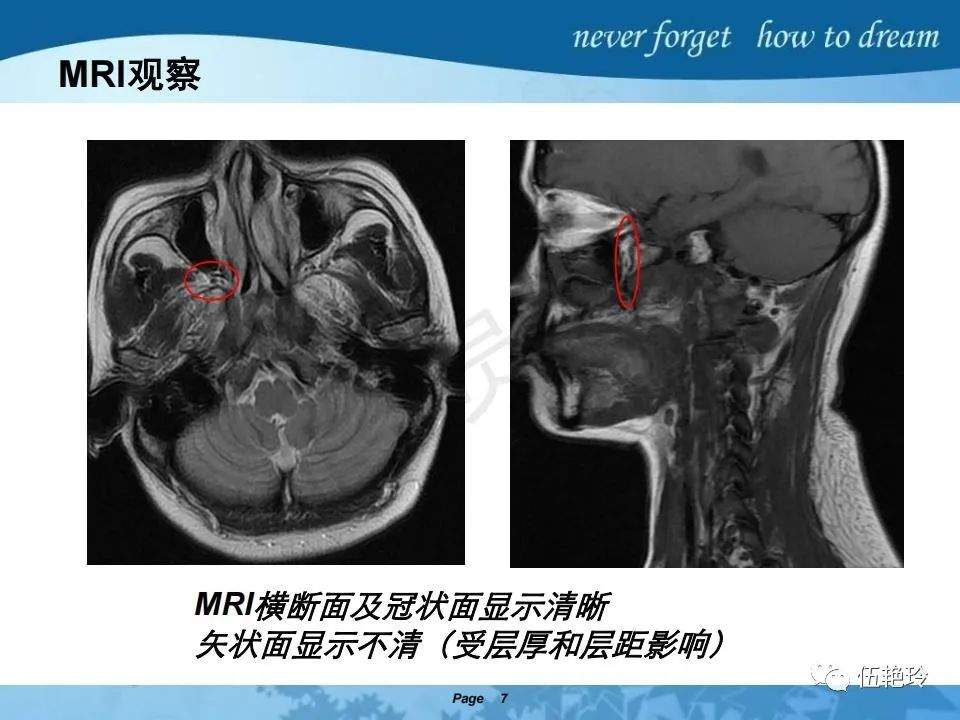

2.61 CT:骨密度增高;MRI:骨髓高信号消失。